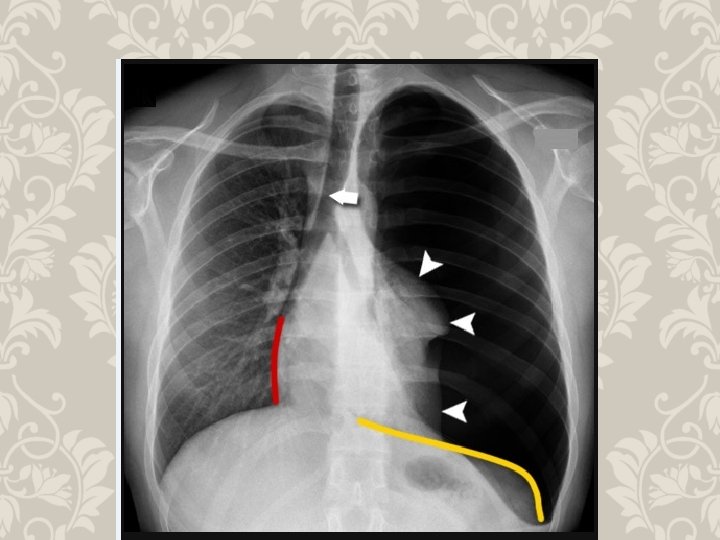

HEMOTHORAX life-threatening injury number one A massive hemothorax is defined as >1500 m. L of blood or, in the pediatric population, one third of the patient's blood volume in the pleural space tube thoracostomy is the only reliable means to quantify the amount of hemothorax After blunt trauma, a hemothorax usually is due to multiple rib fractures occasionally bleeding is from lacerated lung parenchyma a massive hemothorax is an indication for operative intervention Indication of emergency toracotomy

HEMOTHORAX PHYSICAL FINDINGS

RIB FRACTURE WITH HEMOTHORAX